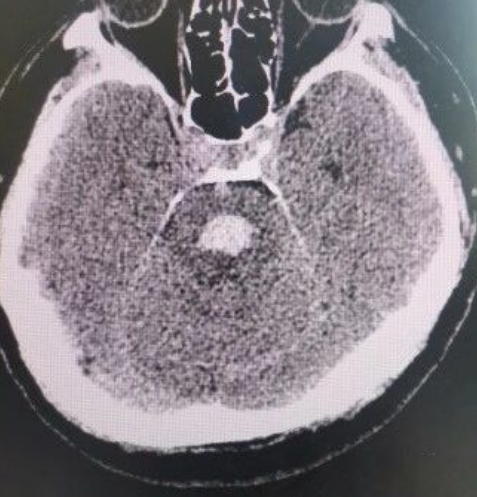

脑部CT影像图

影像结果触目惊心:脑内血管破裂,血肿已形成并压迫脑干!这是神经急危重症中最凶险的情况,随时可能发生脑疝、呼吸心跳骤停。长春国文医院卒中团队立即启动多学科协作机制,神经外科、重症医学科、麻醉科专家迅速完成联合评估,制定抢救方案——控制血压、降低颅压、绝对卧床、止血、减轻脑水肿……每一步都精准而果断。